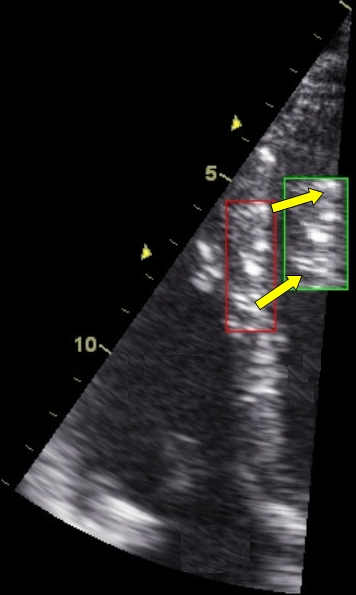

17Academic Journal

Συγγραφείς: I. S. Bessonov, D. V. Krinochkin, V. A. Kuznetsov, A. O. Dyakova, N. Y. Khorkova, N. A. Galeeva, A. A. Takkand, И. С. Бессонов, Д. В. Криночкин, В. А. Кузнецов, А. О. Дьякова, Н. Ю. Хорькова, Н. А. Галеева, А. А. Такканд

Πηγή: Siberian Journal of Clinical and Experimental Medicine; Том 34, № 1 (2019); 137-144 ; Сибирский журнал клинической и экспериментальной медицины; Том 34, № 1 (2019); 137-144 ; 2713-265X ; 2713-2927 ; 10.29001/2073-8552-2019-34-1

Θεματικοί όροι: чрескожное коронарное вмешательство, premature ventricular complex, contrast stress echocardiography, optical coherence tomography, percutaneous coronary intervention, желудочковая экстрасистолия, контрастная стресс-эхокардиография, оптическая когерентная томография

Περιγραφή αρχείου: application/pdf

Relation: https://www.sibjcem.ru/jour/article/view/693/437; Wang H., Abajobir A.A., Abate K.H., Abbafati C., Abbas K.M., Abd-Allah F., et al. Global Burden of Disease 2016 Mortality Collaborators. Global, regional, and national under-5 mortality, adult mortality, agespecific mortality, and life expectancy, 1970–2016: a systematic analysis for the Global Burden of Disease Study 2016. Lancet. 2017;390:1084– 1150. DOI:10.1016/S0140-6736(17)31833-0.; Шальнова С.А., Деев А.Д., Оганов Р.Г. Факторы, влияющие на смертность от сердечно-сосудистых заболеваний в российской популяции. Кардиоваскулярная терапия и профилактика. 2005;4(1):4–8.; Голицын С.П., Кропачева Е.С., Майков Е.Б., Миронов Н.Ю., Панченко Е.П., Соколов С.Ф. и др. Клинические рекомендации диагностика и лечение нарушений ритма сердца и проводимости Часть II. Кардиологический вестник. 2014;9(3):3–52.; Panizo J.G., Barra S., Mellor G., Heck P., Agarwal S. Premature Ventricular Complex-induced Cardiomyopathy. Arrhythmia & Electrophysiology Review. 2018;7(2):128–134. DOI:10.15420/aer.2018.23.2.; Lin C.Y., Chang S.L., Lin Y.J., Chen Y.Y., Lo L.W., Hu Y.F., et al. An observational study on the effect of premature ventricular complex burden on long-term outcome. Medicine (Baltimore). 2017;96(1):e5476. DOI:10.1097/MD.0000000000005476.; Priori S.G., Blomstrom-Lundqvist C., Mazzanti A., Blom N., Borggrefe M., Camm J., et al. 2015 ESC Guidelines for the management of patients with ventricular arrhythmias and the prevention of sudden cardiac Death. The Task Force for the Management of Patients with Ventricular Arrhythmias and the Prevention of Sudden Cardiac Death of the European Society of Cardiology. Eur. Heart J. 2015;36(41):2793–2867. DOI:10.1093/eurheartj/ehv316.; Neumann F.J., Sousa-Uva M., Ahlsson A., Alfonso F., Banning A.P., Benedetto U., et al. 2018 ESC/EACTS Guidelines on myocardial revascularization. Eur. Heart J. 2018;00:1–96. DOI:10.1093/eurheartj/ehy394.; Кузнецов В.А., Самойлова Е.П., Бессонов И.С., Гультяева Е.П., Зырянов И.П., Бердинских С.Г. и др. Отдаленные результаты чрескожных коронарных вмешательств в сравнении с медикаментозной терапией при лечении пациентов со стабильной ишемической болезнью сердца в реальной клинической практике. Российский кардиологический журнал. 2016;2:7–11. DOI:10.15829/1560-4071-2016-2-7-11.; Al-Lamee R., Thompson D., Dehbi H.M., Sen S., Tang K., Davies J., et al. Percutaneous coronary intervention in stable angina (ORBITA): a double-blind, randomised controlled trial. Lancet. 2018;391(10115):31–40. DOI:10.1016/S0140-6736(17)32714-9.; Wijeysundera H.C., Bennell M.C., Qiu F., Ko D.T., Tu J.V., Wijeysundera D.N., et al. Comparative-Effectiveness of Revascularization versus Routine Medical Therapy for Stable Ischemic Heart Disease: A Population-Based Study. J. Gen. Intern. Med. 2014;8:1–9. DOI:10.1007/ s11606-014-2813-1.; Кузнецов В.А., Самойлова Е.П., Бессонов И.С., Гультяева Е.П., Бердинских С.Г., Горбатенко Е.А. и др. Чрескожные коронарные вмешательства в сравнении с медикаментозной терапией у пациентов с хронической ишемической болезнью сердца: результаты отдаленного наблюдения. Consilium medicum. 2018;1:33–37. DOI:10.26442/2075-1753_2018.1.33-37.; Седов В.П., Алехин М.Н., Корнеев Н.В. Стресс-эхокардиография. М.: ЗАО «Информатик»; 2000:152.; Rieber J., Jung P., Erhard I., Koenig A., Hacker M., Schiele T.M., et al. Comparison of pressure measurement, dobutamine contrast stress echocardiography and SPECT for the evaluation of intermediate coronary stenoses. The COMPRESS trial. Int. J. Cardiovasc. Intervent. 2004;6(3–4): 142–147. DOI:10.1080/14628840410030504.; Montalescot G., Sechtem U., Achenbach S., Andreotti F., Arden C., Budaj A., et al. ESC guidelines on the management of stable coronary artery disease. The Task Force on the management of stable coronary artery disease of the European Society of Cardiology. Eur. Heart J. 2013;34(38):2949–3003. DOI:10.1093/eurheartj/eht296.; Senior R., Becher H., Monaghan M., Agati L., Zamorano J., Vanoverschelde J.L., et al. Clinical practice of contrast echocardiography: recommendation by the European Association of Cardiovascular Imaging (EACVI) 2017. Eur. Heart J. — Cardiovasc. Imaging. 2017;18(11):1205– 1205af. DOI:10.1093/ehjci/jex182.; Gaibazzi N., Rigo F., Squeri A., Ugo F., Reverberi C. Incremental value of contrast myocardial perfusion to detect intermediate versus severe coronary artery stenosis during stress-echocardiography. Cardiovasc. Ultrasound. 2010;8(1):16. DOI:10.1186/1476-7120-8-16.; Даренский Д.И., Жарова Е.А., Матчин Ю.Г. Инвазивные методы определения функциональной значимости коронарных стенозов пограничной степени выраженности. Кардиологический вестник. 2016;11(2):80–89.; https://www.sibjcem.ru/jour/article/view/693